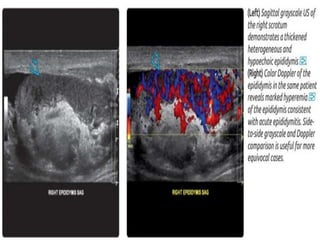

Doppler Ultrasound of the testis  Hypervasularity

Colour duplex

Doppler

ultrasonography.

• Is The imaging

modality of choice

for diagnosing

testicular torsion

• Colour Doppler

ultrasound will

show reduced

arterial blood flow

to the involved

testicle.